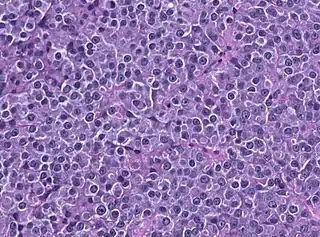

Un prolactinoma es un tumor secretante (adenoma) de la adenohipófisis, cuyas células (los lactotropos) segregan Prolactina, esto produce concentraciones elevadas de esta hormona, condición denominada hiperprolactinemia.[2]

Los prolactinomas son tumores benignos, rara vez sufren transformación maligna o invasividad local. Se ha propuesto que los prolactinomas tienen un origen monoclonal y que las alteraciones en la regulación del ciclo celular conducen a la expansión de una célula original mutada.[3]